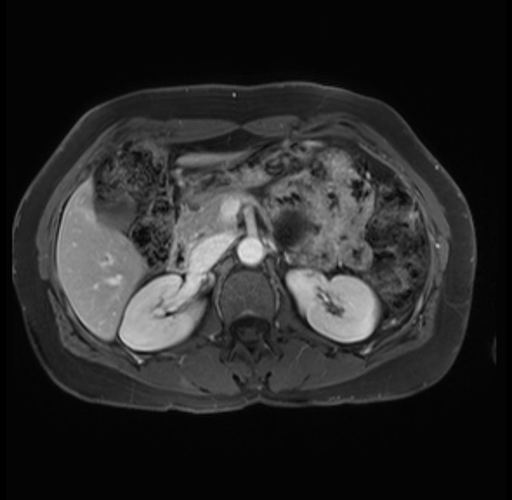

Imaging Analysis

Look through the patient's CT scan to identify any areas of concern for the necessary procedure.

Based on your CT findings, which issue(s) are present and would give reason for "planned slowing down moment(s)" in this case?

Considering a standard distal pancreatectomy procedure, what step(s) of the operation would you do differently in this case?